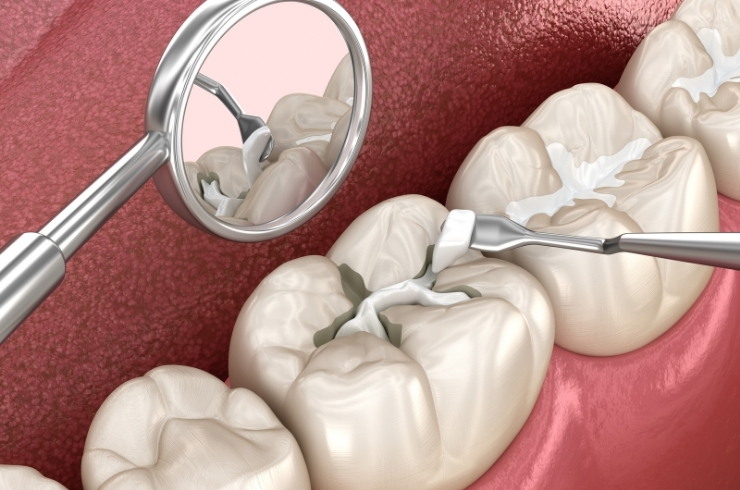

Dental Sealant

Protective coating applied to molars to prevent cavities, seal deep grooves, and promote long-term oral health, especially in children and teens.